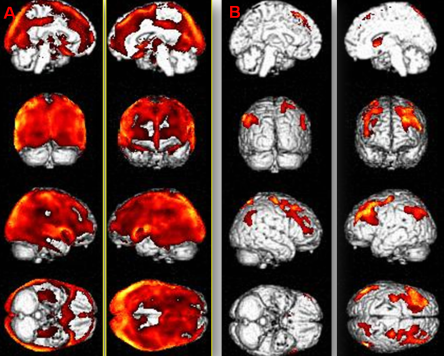

如图:同样被诊断为植物状态的两名患者的功能神经影像(PET-CT)。图中红色的区域为大脑受到抑制的低代谢区域,可见A图的抑制面积很大,像一顶“钢盔”覆盖了大脑半球;而B图只有部分受到抑制。两名患者都被诊断为植物状态,但是经过治疗预后具有明显差异。A患者一直未清醒,而B患者就是我们文章中列举的例子,已经清醒。